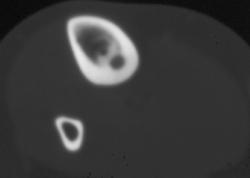

CASE NUMBER 483

Psoas Abscess